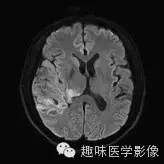

【病例】少突胶质细胞瘤1例MR影像表现

性别:男年龄:48岁 间断性四肢抽搐9月余,头晕伴肢体无力1月余

[影像表现]

右侧颞顶叶、丘脑可见大片不规则异常信号灶,局部脑回肿胀,大小约45×75mm,T1WI呈混杂低信号,内可见多发条状高信号,中央可见更低信号灶,T2WI/FLAIR呈混杂稍高信号,内可见点状低信号,DWI呈混杂高信号,未见明显占位效应,增强后呈多发不规则花环状明显强化灶,内可见多发点状小血管影。